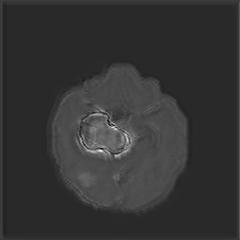

(a) (b) (c) (d)

Boundary Stream:

Fig. 2 demonstrates the output of each of the attention layers in our dedicated boundary stream. In essence, each attention layer progressively localizes the tumor and refines the boundaries. The first attention layer has learned rough estimate of the boundaries around the tumor and localized it, whereas the second and third layers have learned more fine-grained details of the edges and boundaries, refining the localization. Moreover, since our architecture leverages a dilated spatial pyramid pooling to merge the learned feature maps of the regular segmentation stream and the boundary stream, multiscale regional and boundary information have been preserved and fused properly, which has enabled our network to capture the small structural details of the tumor.